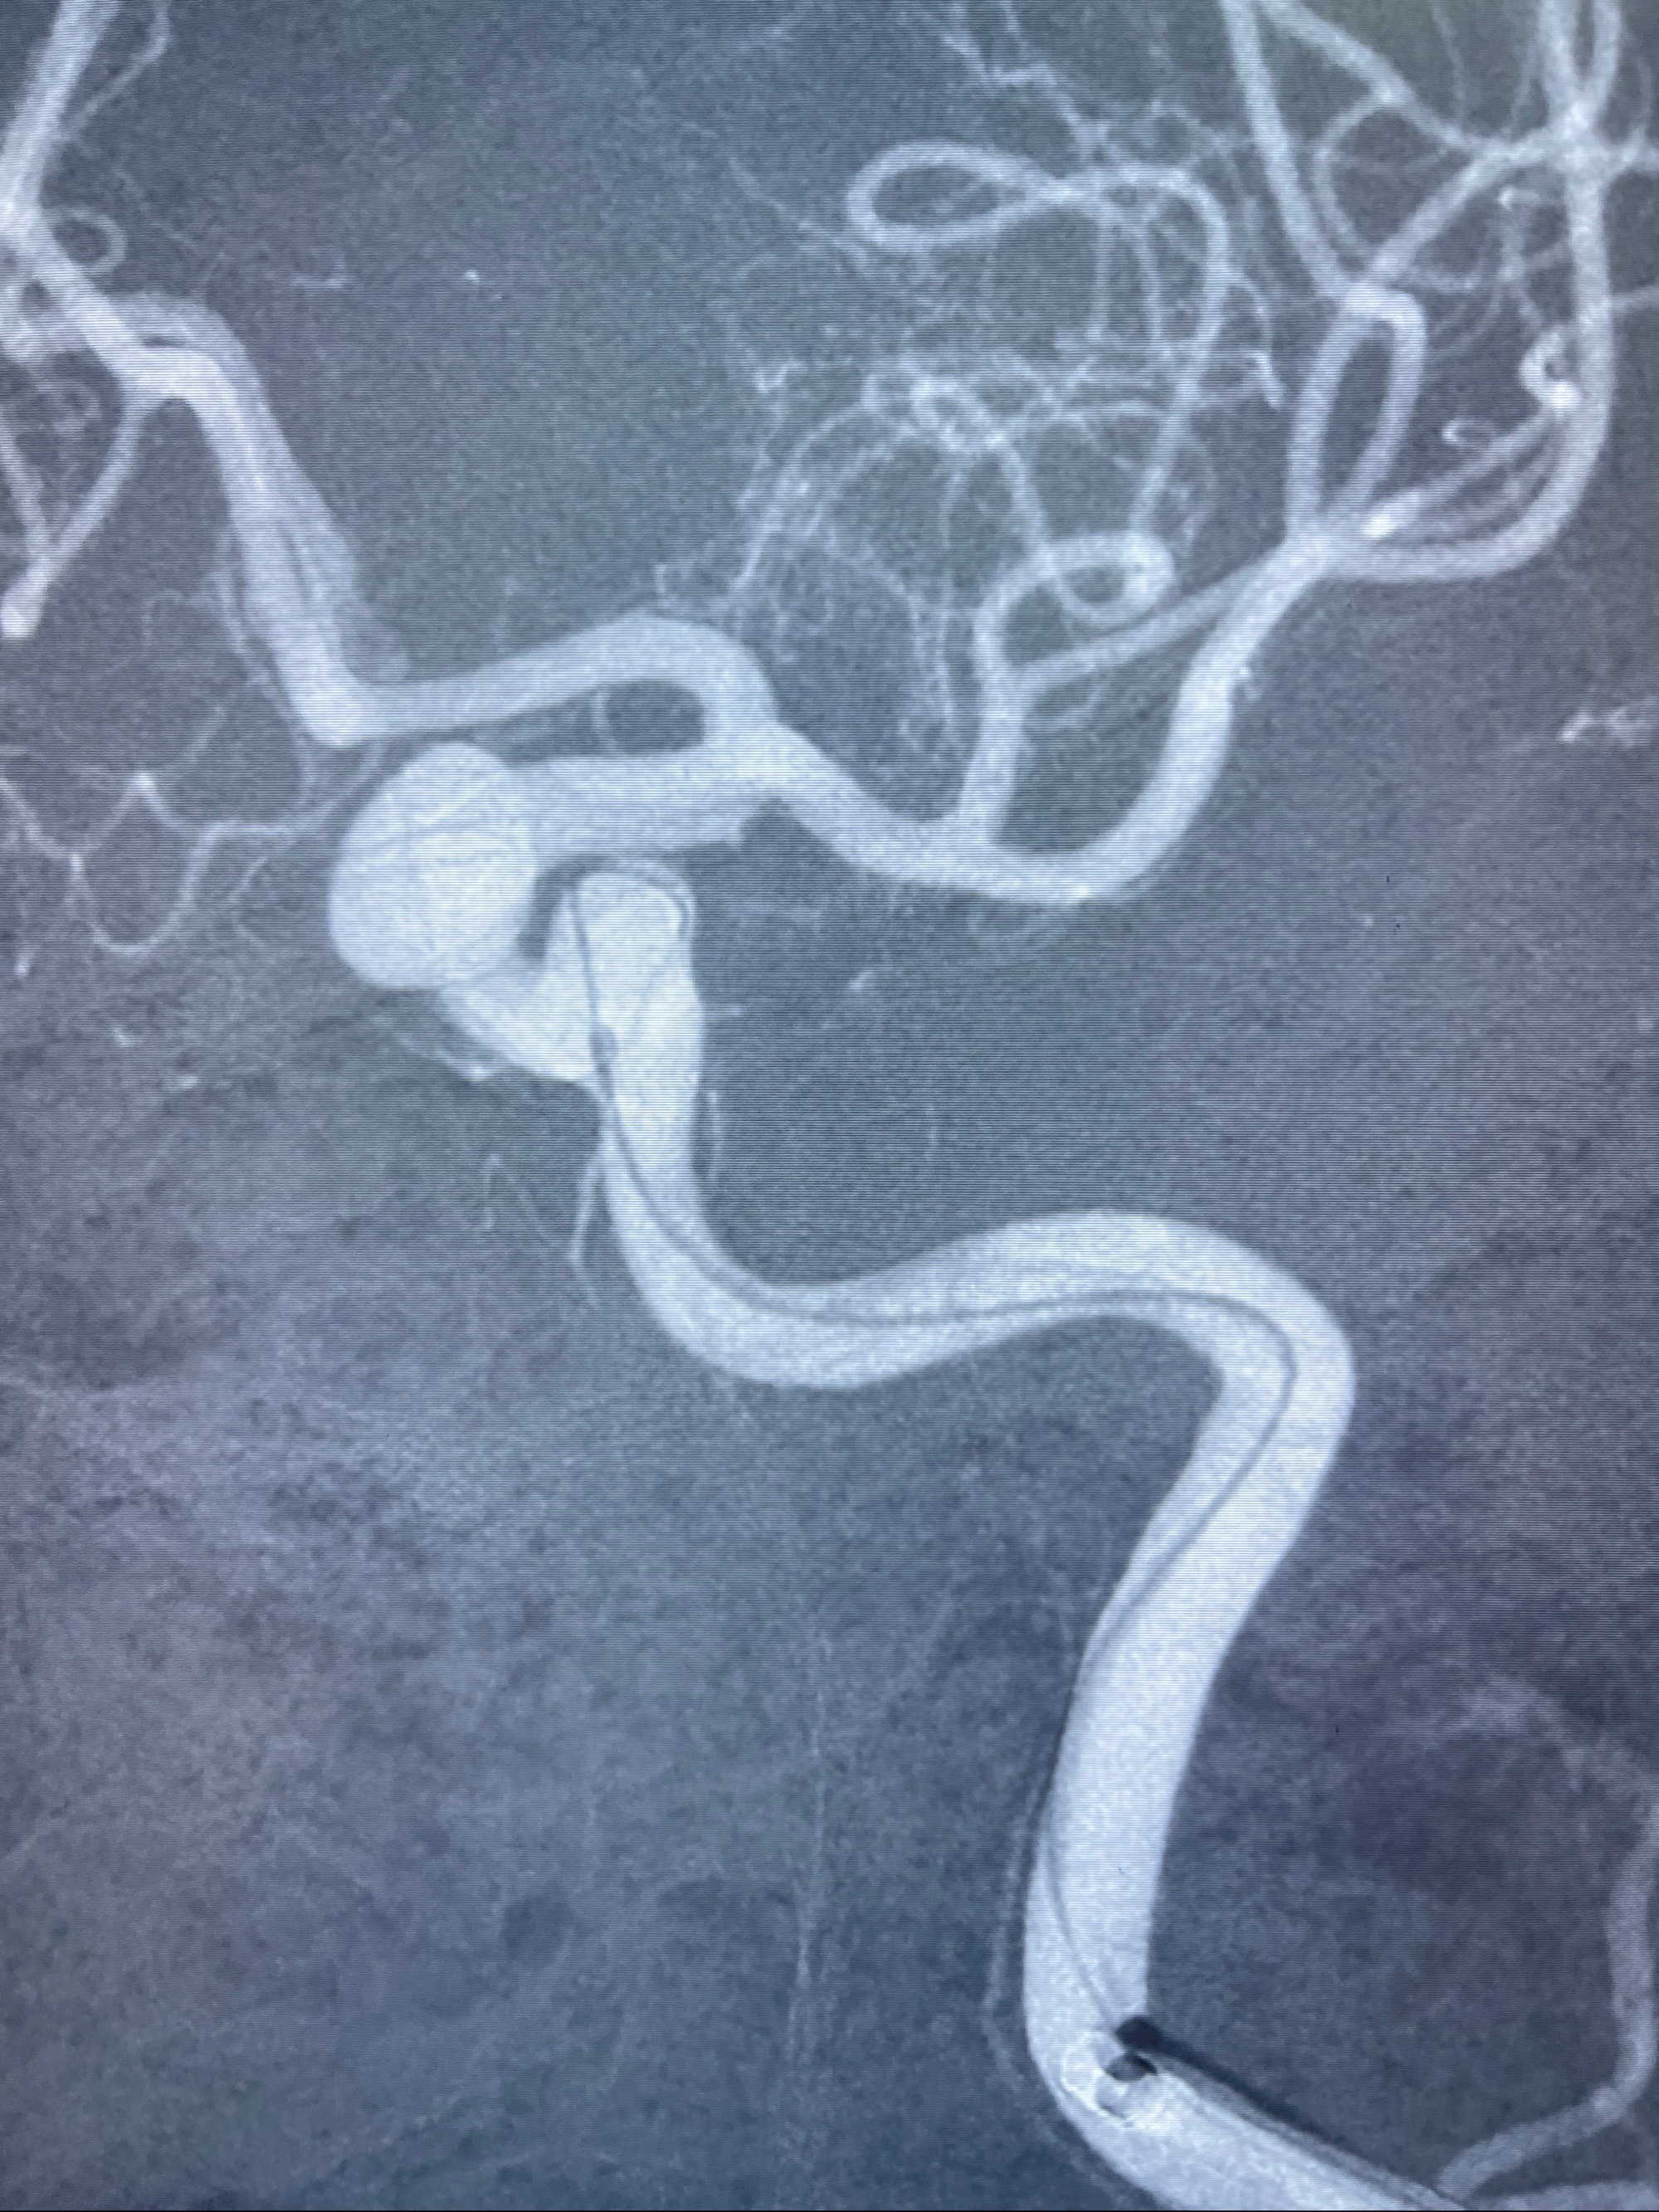

2023-08-30DSA:左侧颈内动脉眼动脉动脉瘤,约3*9.2*7.3mm大小

- Tubridge 4.0-20mm密网支架

术后3D显示支架贴壁佳